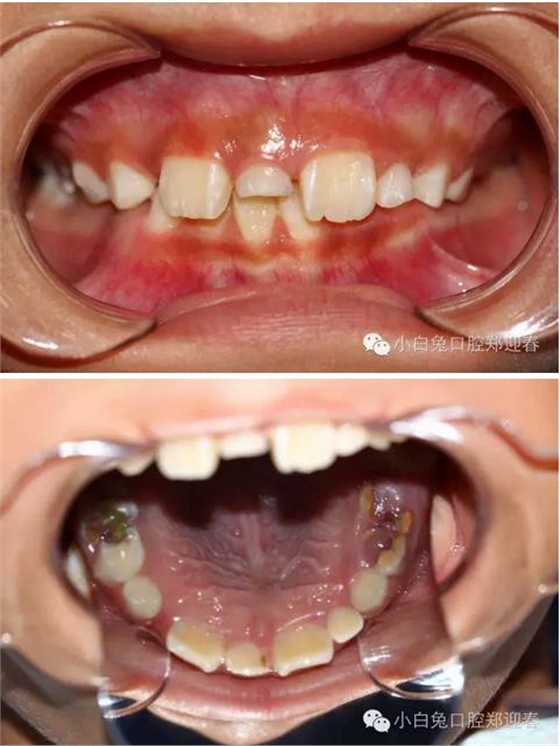

患兒,男,8歲半,混合牙列,11、12均已萌出,其間有一重度磨耗的51滯留,家長一直不知怎么回事,因為美觀問題,至當?shù)卦\所給予檢查,也許條件受限沒有X光牙片機的緣故,建議直接拔除51,然后矯正關(guān)閉間隙,家長不放心,來診,常規(guī)拍攝X線片發(fā)現(xiàn)乳牙滯留和間隙存在的原因是有一埋伏倒置多生牙的緣故,遂建議拔除滯留的51和埋伏的多生牙,然后擇期矯正。

X線片:51牙根基本吸收,下方顯示倒置多生牙。